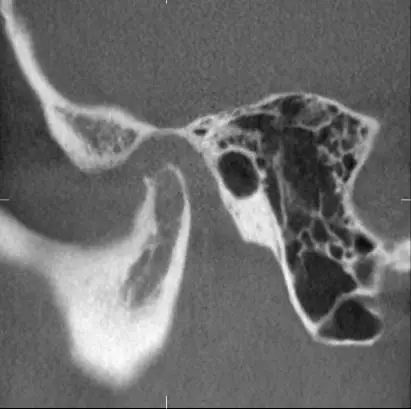

甚至髁突吸收:

640.webp.jpg

640.webp (1).jpg

所以,這種智齒也還是要 拔掉。